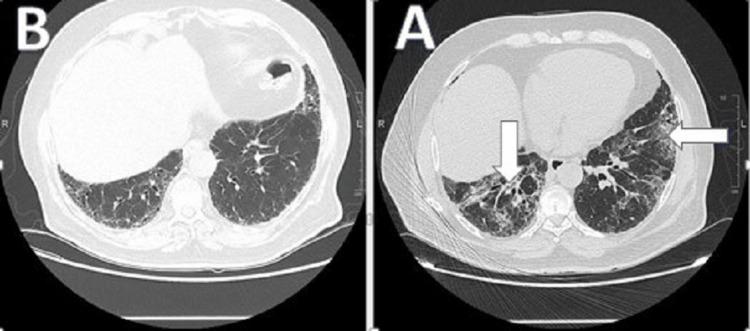

Metformin, a mainstay treatment for type two diabetes mellitus has several side effects, ranging from mild to life-threatening ones. One report has found the combination of metformin/glibenclamide a culprit for interstitial lung disease. Other studies have shown that metformin has a protective effect on the lungs. We report a rare case of a 64-year-old male who presented with progressive dyspnea while he was on metformin alone. He was diagnosed with eosinophilic interstitial lung disease (ILD). This was confirmed by a pulmonary function test (PFT), high-resolution chest computed tomography scan (HRCT), and bronchoscopy with bronchoalveolar lavage (BAL). Known causes for eosinophilic pneumonia were excluded, and the patient's condition improved significantly after withdrawing metformin. We report this case due to the rarity of the condition. In fact, this is the only case in the literature, of metformin as the sole agent causing eosinophilic pneumonitis.